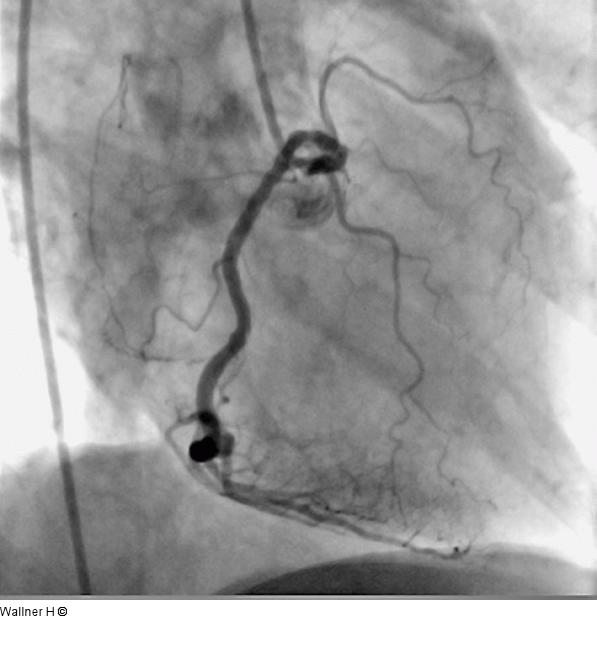

Abbildung 8: Perkutane koronare Intervention Rotationsangiographie |

Abbildung 8: Perkutane koronare Intervention

Rotationsangiographie |